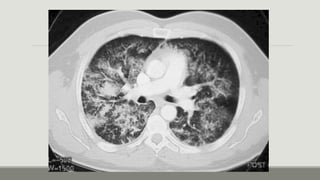

Rx de tórax

Fase

intersticial:

Pérdida de la definición de los vasos

pulmonares, engrosamiento de los

tabiques interlobulillares (líneas A y B de

Kerley), nódulos acinares perhiliares,

manguitos peribronquiales,

engrosamiento de las cisuras.

alveolar:

Patrones alveolares mal definidos, confluentes, con

distribución parcheada, bordes irregulares y

predominante en el tercio interno del pulmón,

patrón en ¨alas de mariposa’ (la consolidación se

extiende desde la región perhiliar hacia afuera,

dejando no daño a la zona subpleural)